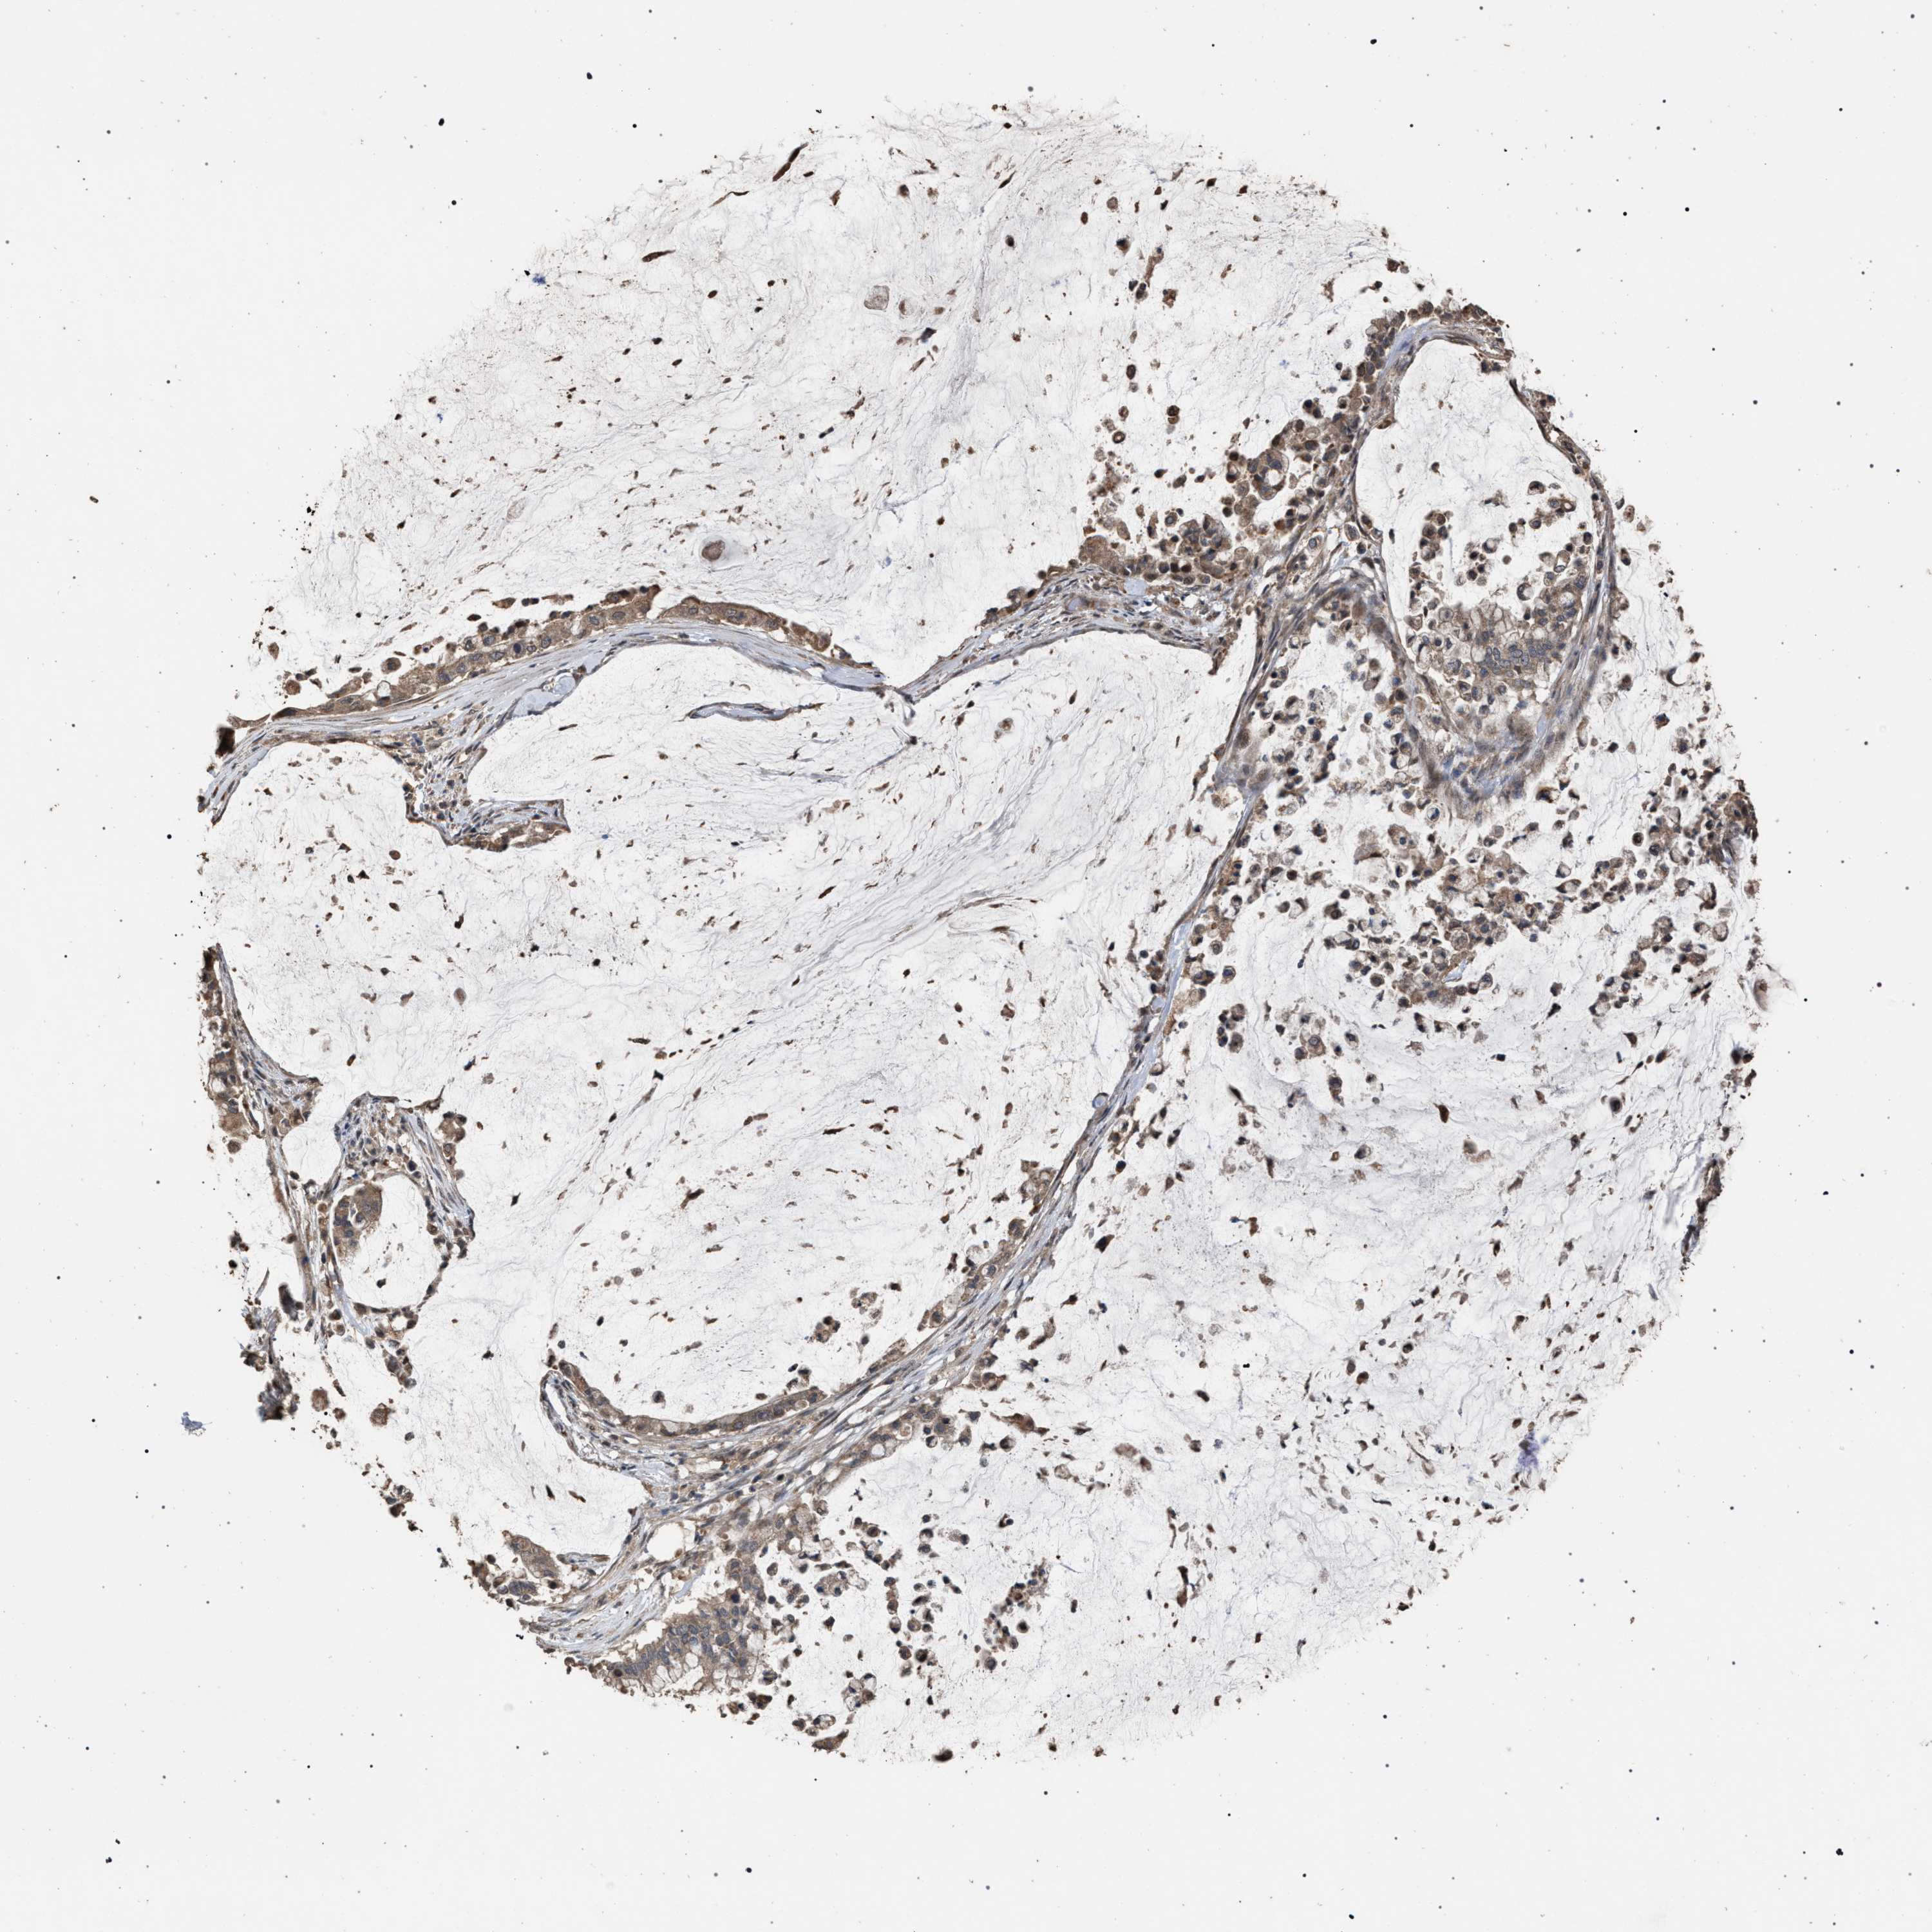

PANCREATIC CANCER - Protein expressioni

A mouse-over function shows sample information and annotation data. Click on an image to view it in a full screen mode. Samples can be filtered based on level of antibody staining by selecting one or several of the following categories: high, medium, low and not detected. The assay and annotation is described here.

Note that samples used for immunohistochemistry by the Human Protein Atlas do not correspond to samples in the TCGA dataset.

Antibody stainingi

Antibody staining in the annotated cell types in the current human tissue is reported as not detected, low, medium, or high, based on conventional immunohistochemistry profiling in selected tissues. This score is based on the combination of the staining intensity and fraction of stained cells.

Each image is clickable and will lead to virtual microscopy that enables deeper exploration of all samples and also displays staining intensity scores, fraction scores and subcellular localization as well as patient and tissue information for each sample.

Antibody HPA021547

Staining

High

Medium

Low

Not detected

Intensity

Strong

Moderate

Weak

Negative

Quantity

>75%

75%-25%

<25%

None

Location

Nuclear

Cytoplasmic/membranous

Cytoplasmic/membranous,nuclear

Adenocarcinoma, NOS